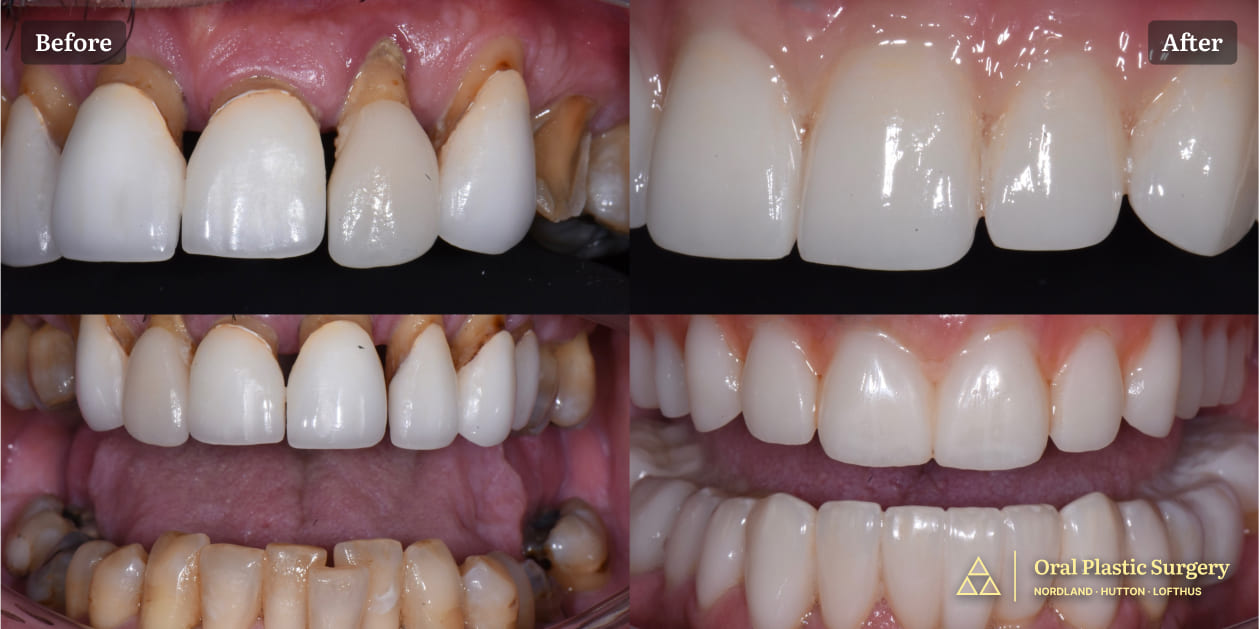

A full smile transformation: loose, painful teeth were removed and replaced with a stable, implant-supported restoration.

Surgery Day: Diseased teeth were removed, bone was prepared, and seven implants were placed. Phil left the office the same day with a full provisional restoration and a confident new smile.

Final Prosthesis: After tissue healing, Cyber Ceramics fabricated natural-looking zirconia-porcelain teeth. They seated seamlessly and fit perfectly from the first day.

The zirconia-porcelain teeth displayed lifelike translucency and esthetics indistinguishable from natural dentition.